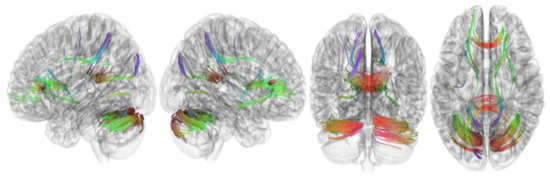

3.2. Tracks with FA Correlated with RLS Severity

| Tracks with positive correlation with RLS severity | Cerebellum, corpus callosum forceps minor, corpus callosum forceps major, corpus callosum body, and cingulum frontoparietal track |

| Tracks with negative correlation with RLS severity | Middle cerebellar peduncle, inferior longitudinal fasciculus, corticospinal tract, corpus callosum forceps minor, cerebellum, frontal aslant tract, dentato-rubrothalamic tract, inferior longitudinal fasciculus, corticostriatal tract superior, and cingulum parahippocampoparietal tract |